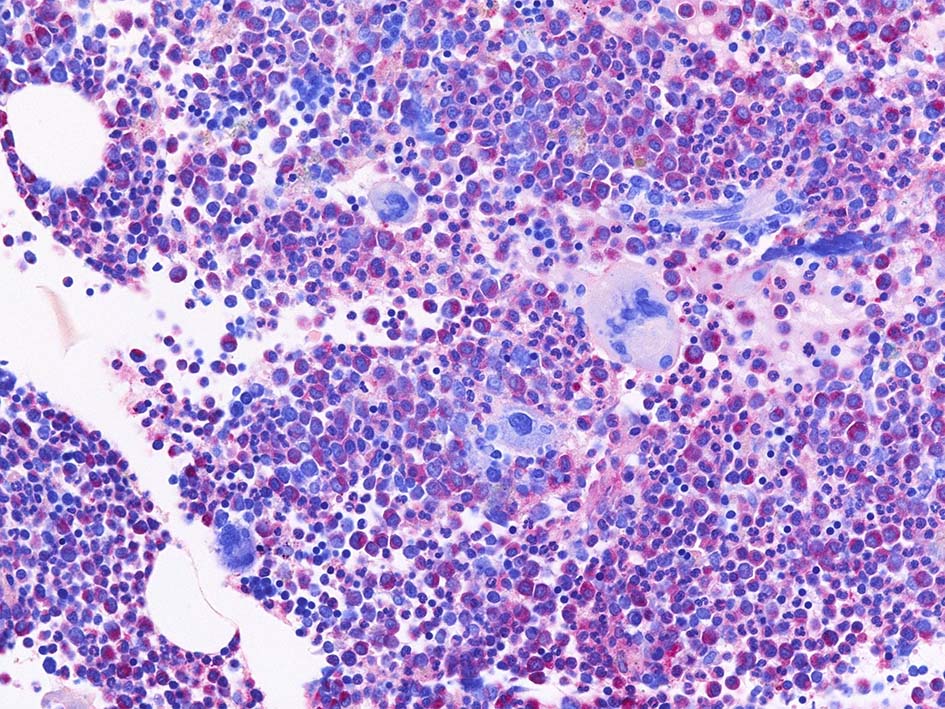

Naphtohl-ASD-CAE Fig.02

Fig.02: 幼若な顆粒球が増加している. 赤芽球は散在しており血島は不明瞭である. 過形成髄なのにFig.02に成熟大型巨核球はみられない.

Fig.03: granulopoietic hyperplasia. 成熟顆粒球の増加もある.